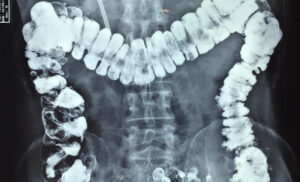

Colon por enema.

Consiste en introducir a través del ano una pintura y después tomar varias radiografías del abdomen de tal manera que se dibuje con precisión la anatomía del colon. En caso de una fístula anorrectal puede ser útil para descartar enfermedades asociadas o diagnosticar causas poco comúnes de fístula anorrectal, como los divertículos de colon.